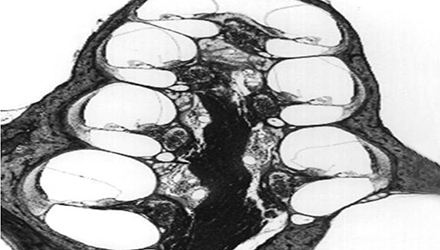

膜迷路積水致膜迷路脹破,內外淋巴液混合,刺激神經感覺細胞導致眩暈、耳鳴、耳聾,裂口愈合則病變暫時恢復。下圖左為前庭膜膨大,右圖為前庭膜破裂,內外淋巴交混。